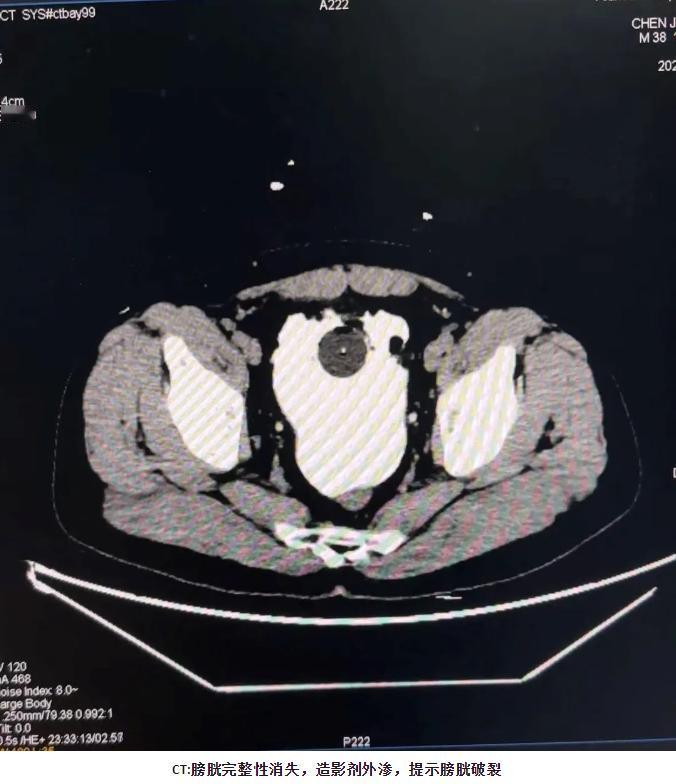

10月,陕西一男子和朋友喝酒,连喝8瓶都没上厕所,回到家发现明明想撒尿却尿不出来了,去医院检查才发现,膀胱已经破了一个6cm的大洞!网友:这也太能“憋”了。 西安某医院病房里,李先生掀开衣服露出术后疤痕。6厘米长的淡粉色印记横在小腹,这是他喝8瓶啤酒憋尿后,膀胱破裂留下的痕迹。 他捏着复查报告,声音发哑:“再也不敢拿命逞强了。” 事发那天傍晚,李先生和朋友约在饭馆聚餐。刚坐定,朋友就笑着起哄:“谁先去厕所谁买单。”李先生好面子,拍着胸脯应下来。从七点到十一点,啤酒一瓶接一瓶空了瓶。 他尿意翻涌时,就喝口茶压一压,始终没起身。朋友劝他“别硬撑”,他还说“没事,我肾功能好”。 散场时,李先生脚步虚浮地往家走。冷风一吹,他打了个寒颤,肚子隐隐发紧。到家后倒头就睡,没把这点不适放在心上。凌晨一点,剧烈的腹痛把他从梦里拽醒。 他捂着肚子冲进厕所,却只挤出几滴尿。冷汗顺着额头往下淌,他蹲在地上喊出声。 妻子听见动静,赶紧跑过来扶他。看到他脸色惨白,说话都没力气,立刻拨了120。救护车往医院赶时,李先生疼得蜷缩在担架上。他还断断续续念叨:“就是憋了会儿尿,怎么会这样。” 那时他不知道,膀胱早已胀得超出极限,裂了道大口子。 到医院急诊室,医生按压他的腹部。李先生疼得大叫,医生立刻安排CT检查。报告出来时,医生皱着眉说:“腹腔里全是积液。”进一步检查发现,积液是淡红色的尿液和炎性渗出物。 “膀胱破了个6厘米的洞,必须马上手术。”妻子签手术同意书时,手都在抖。 手术从凌晨三点做到六点多。医生后来跟家属解释,啤酒有利尿作用。正常人膀胱容量约500毫升,李先生撑到了1500毫升以上。“膀胱壁被撑薄,再加上酒精刺激,就破裂了。” 还好手术及时,没伤到其他器官,也没引发感染。 术后第一天,李先生清醒过来。看到手背上的输液管,还有小腹的纱布,他愣了好久。医生查房时,特意叮嘱他恢复期注意事项。“三个月内不能憋尿,不能剧烈运动,还要定期复查。” 他点点头,心里满是后悔,当初不该跟朋友赌这口气。 同病房的大爷听说他的经历,也打开了话匣子。“我之前憋得尿血,查出尿路感染,住了一周院。”大爷劝他:“身体是自己的,别为了面子遭罪。”李先生听着,把这话记在了心里。 术后一周,李先生能下床慢慢走了。朋友来看他,带着水果和营养品,满脸愧疚。“都怪我们起哄,以后再也不搞这种赌约了。”李先生摆摆手:“不怪你们,是我自己太逞强。” 朋友临走前说:“以后喝酒,咱们谁想上厕所就去。” 出院那天,妻子帮他收拾东西。反复确认复查时间和注意事项,才推着轮椅走。回家路上,李先生看着窗外,心里五味杂陈。以前总觉得憋尿是“能耐”,现在才知道多危险。 他掏出手机,在社交平台发了自己的经历。配文很简单:“别拿憋尿当本事,我这疤痕就是教训。” 评论区里,很多人分享类似的遭遇。有人说自己憋尿导致膀胱炎,疼了好几天。有人说父亲憋尿查出膀胱结石,花了不少钱治疗。李先生一条条看,还回复“别大意,及时就医”。 他想让更多人知道,憋尿不是小事,可能危及健康。 如今,李先生已经恢复得差不多了。每天按时吃药,定期去医院复查。医生说他恢复得不错,疤痕会慢慢变淡。他推掉了所有酒局,就算朋友聚餐也只喝果汁。 只要有尿意,他马上就去厕所,再也不硬撑。有时看到别人在酒桌上逞强,他还会忍不住劝两句。他常说:“面子没那么重要,身体健康才是真的。” 信息来源:《男子豪饮8瓶啤酒,尿意十足却仅有几滴排出,医生:膀胱撑出6cm巨大破口》成都商报红星新闻